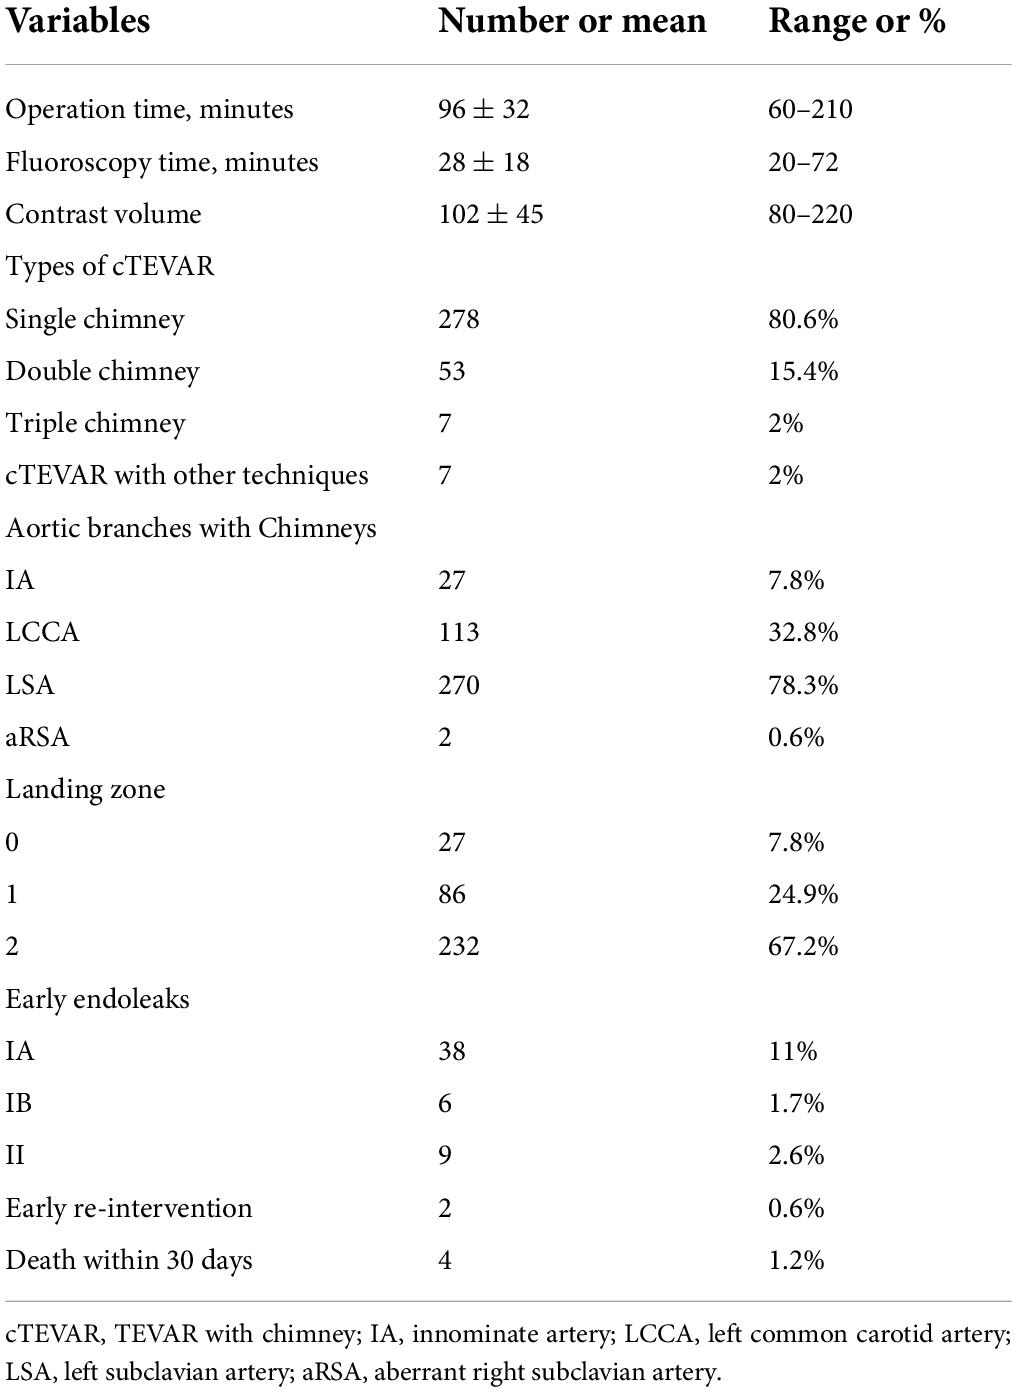

During follow-up, the type IA endoleak disappeared spontaneously in 14 patients, while three patients with progressively increased type IA endoleak received the secondary intervention (two with coil embolization and one with LSA chimney stent angioplasty). As shown in Figure 2, the patient underwent TEVAR with a chimney stent deployed in LCCA and duct occluder in LSA. He showed progressed type IA endoleak after TEVAR and received coil embolization 4 years later, and then the endoleak totally resolved. The remaining 16 patients with persistent type IA endoleak continued to be monitored with close surveillance. Thus, the rate of persistent and re-intervened type IA endoleak was 5.5% (19/345). Type II endoleak from LSA disappeared spontaneously in two patients, two patients with progressed type II endoleak were re-intervened (one with duct occluder and the other with one more stent deployed in LSA and angioplasty). The rest of the two patients with persistent type II endoleak continued to be managed with conservative treatment.

Figure 2. Coil embolization for type IA endoleak 4 years after cTEVAR. Preoperative computed tomography angiography (CTA) showed aortic dissection involving the arch (A). The patient underwent cTEVAR with a chimney stent implanted in LCCA and duct occluder implanted in LSA, and postoperative CTA showed a type IA endoleak (B). The follow-up CTA 4 years later showed the endoleak was significant enlarged (C). With the catheter located in ascending aorta, an angiogram showed contrast could enter the false lumen (D). With the catheter located in LSA, the angiogram showed no contrast entering false lumen (E). With the catheter located in the false lumen, an angiogram showed contrast could enter the aorta (F). After deployment of coils in the false lumen, an angiogram showed contrast could not enter the aorta (G). Post-intervention angiogram (H) and CTA (I) showed the endoleak completely disappeared. cTEVAR, TEVAR with chimney; CTA, computed tomography angiography; LCCA, left common carotid artery; LSA, left subclavian artery; aRSA, aberrant right subclavian artery.